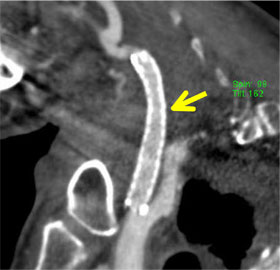

図2 CTによる動脈の描出です。頸動脈とその動脈に留置されているステント(矢印)と呼ばれる狭くなった内腔を拡げるバネが明瞭に描出されています。しかしこの検査も直接動脈検査と同様に大型機械や造影剤を必要としますし放射線被曝があります。 |